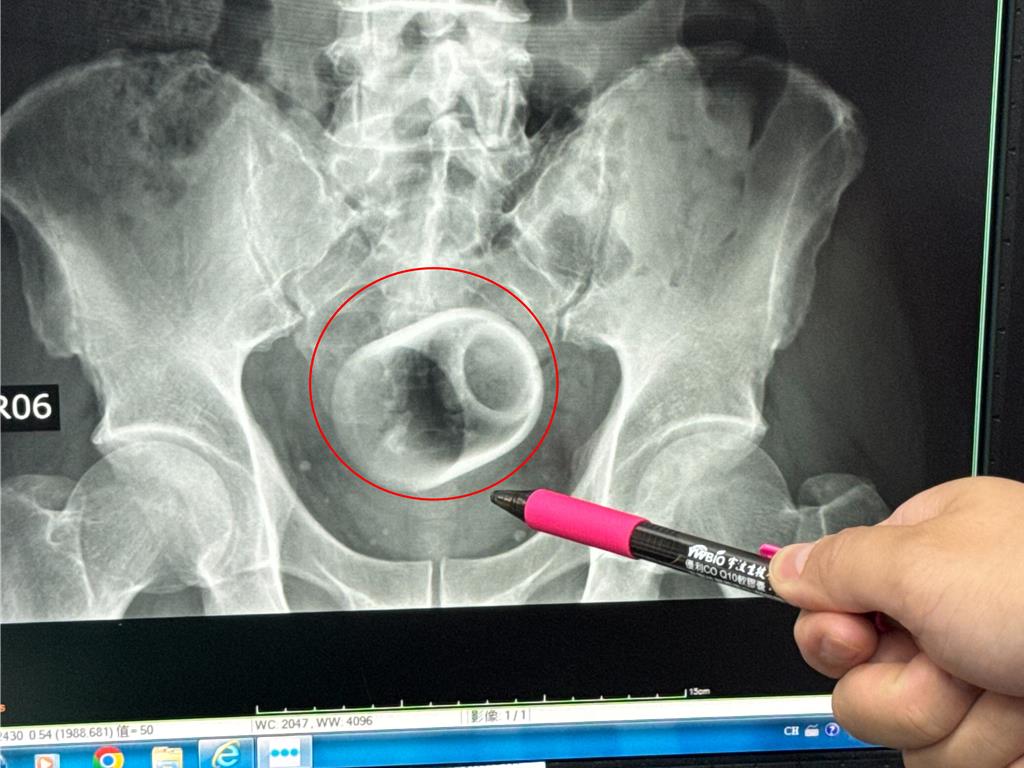

該名患者到院時稱,已經3天無法大便很困擾,害羞不敢提及自己肛門塞了一個杯子,經過X光攝影,可見骨盆腔內有一個直徑約6公分、高約8公分的杯子,杯口朝下,自己當時見狀嚇一大跳,立即安排進手術室,要把杯子拿出來。

醫師起初使用器械要把杯子夾出來,但因杯子光滑無法施力,加上杯身全被大腸包住,部分腸子缺血也造成壞死,後來再使用腹腔鏡,依舊無法順利取出,也擔心把杯子夾碎,傷及患者或造成感染風險,最後只好在肚子上動刀畫開腸子,手術總共歷經2個多小時,最終才取出杯子,同時做好一個人工造口,讓患者能夠暫時解便。